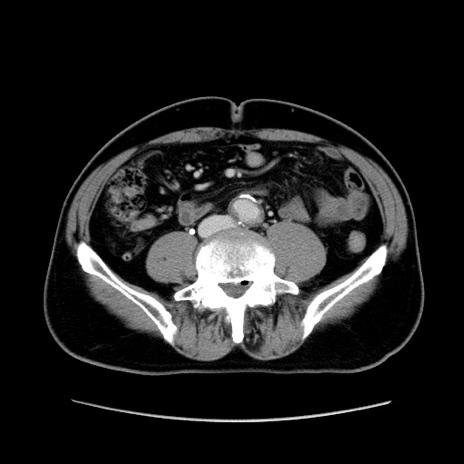

症例34(横断像)

【症例】60歳代 男性

【主訴】右鼠径部膨隆

【現病歴】1年程前より右鼠径部膨隆あり。自己にて還納可能だったため放置していた。3時間前より右鼠径部の脱出を認め、還納困難となり受診。

【身体所見】右鼠径部に小児頭大の膨隆あり。弾性硬であり、用手還納は困難。左鼠径部にも膨隆を認める。脱出はなし。

【データ】WBC 15500、CRP 測定なし